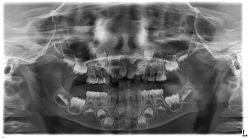

• -青苗儿童口腔(长楹天街购物中心)

相册

晔子_6763 上传于 20-09-20 | 报错